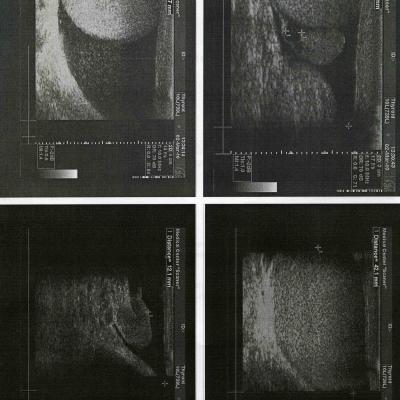

Здравствуйте! Помогите разобраться в такой проблеме. Был на приеме у уролога, сдавал анализы ПЦР на скрытые инфекции(назначил терапевт при обращение с проблемой суставов ног). Врач сделал два мазка, результаты анализов все отр. Через 4 дня появилась опухоль мошонки, с права с верху над яичком. Я опять обратился к тому же урологу, с проблемой опухоли, но врач сказал, что ничего страшного и это подкожная опухоль и все пройдет. Я сделал УЗИ, результаты прикрепляю. Что может быть? Я очень волнуюсь, ведь опухоль просто так не появляется.

Не вижу на узи ничего патологического